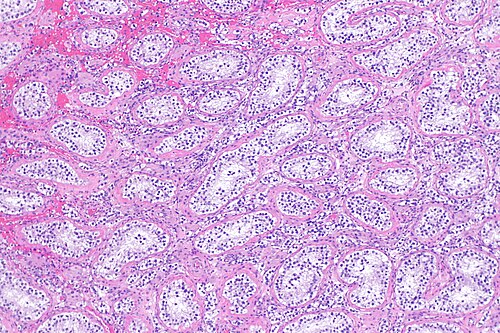

1

Diagnosis?

Atrophic changes of the testis -- intermed mag.jpg

Adenomatoid tumour

Adenocarcinoma of the rete testis

Adenomatous hyperplasia of the rete testis

Benign testis

Atrophic testis

Choriocarcinoma

Embryonal carcinoma

Immature teratoma

Infarcted testis

Inflamed testis

Intratubular germ cell neoplasia

Leydig cell tumour

Lymphoma

Mature teratoma

Mixed germ cell tumour

Papillary cystadenoma of the epididymis

Seminoma

Spermatocytic seminoma

Sertoli cell tumour

Sertoli cell nodule

Testicular scar

Yolk sac tumour